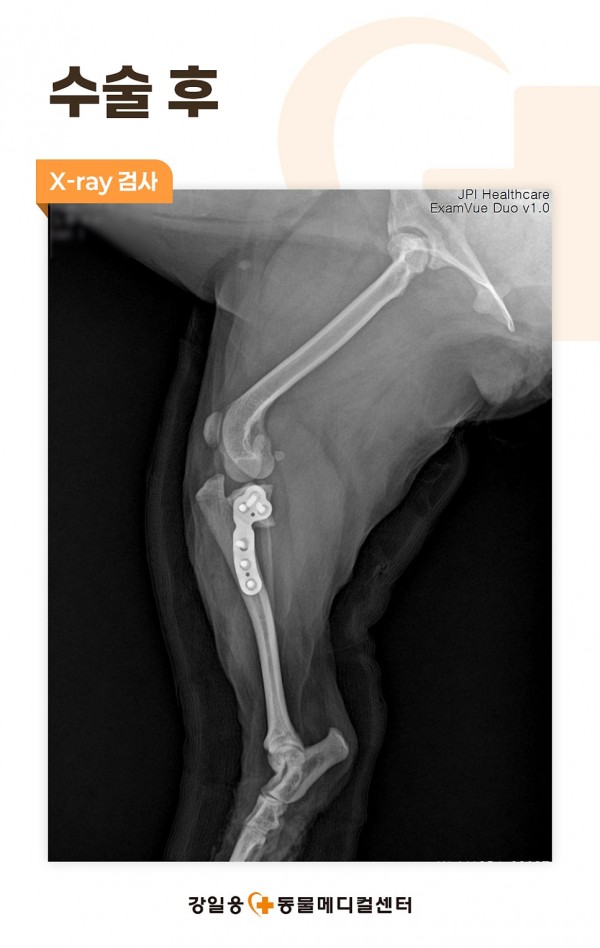

진행된 신체검사상 좌측 drawer sign이 확인되었으며,

더 정확한 진단을 위해 X-ray 검사를 실시하였습니다.

강아지 TPLO 수술

강아지 TPLO(Tibial Plateau Leveling Osteotomy) 수술은

강아지 십자인대파열 치료를 위해 시행되는 대표적인 정형외과 수술 방법 중 하나입니다.

십자인대가 파열되면 보행 시 무릎관절에 앞으로 밀리는 힘이 발생하게 되는데,

TPLO 수술은 경골 고원의 각도를 조절하여 이러한 전방 전위력을 제거함으로써

십자인대가 없어도 무릎관절이 안정적으로 기능할 수 있도록 만들어주는 수술입니다.

끊어진 인대를 직접 봉합하는 방식이 아니라 무릎관절의 구조 자체를 교정하여

관절의 불안정성을 근본적으로 해결하는 데 목적이 있기 때문에 비만,

중·대형견이나 활동량이 많은 강아지, 완전 파열이 진단된 경우에서 특히 좋은 예후를 보입니다.